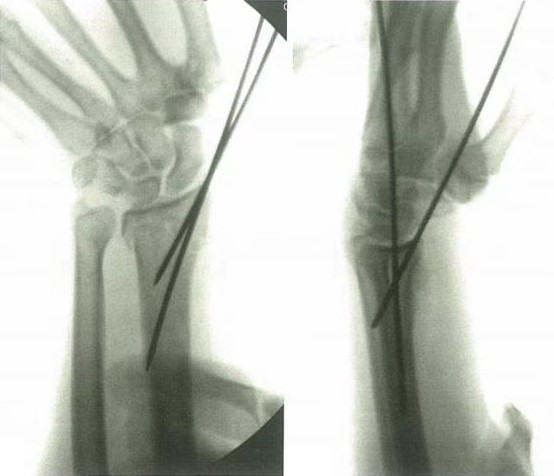

Закрытое восстановление с последующим чрескожным закреплением и фиксацией полезно при переломах дистального радиуса с метафизарной нестабильностью или простыми внутрисуставными переломами.

Первым шагом является анатомическое перемещение, а затем стабилизация обеспечивается грамовыми булавками. Обычно первый штифт передается от радиального стилоида к радиальному метафизом, медиальному в диафиз.

Минимум 2 штифта используются для обеспечения адекватного стабильного перепозиции в ортогональных и боковых положениях, и при желании можно закрепить лунную аспекту.

Внутренняя закрепление (техника Капанджи) обеспечивает дорсальную поддержку. Послеоперационная иммобилизация в шине применяется в течение 2 недель для контроля вращения и минимизации раздражения штифта, после чего ее можно заменить на мягкий лист предплечья.